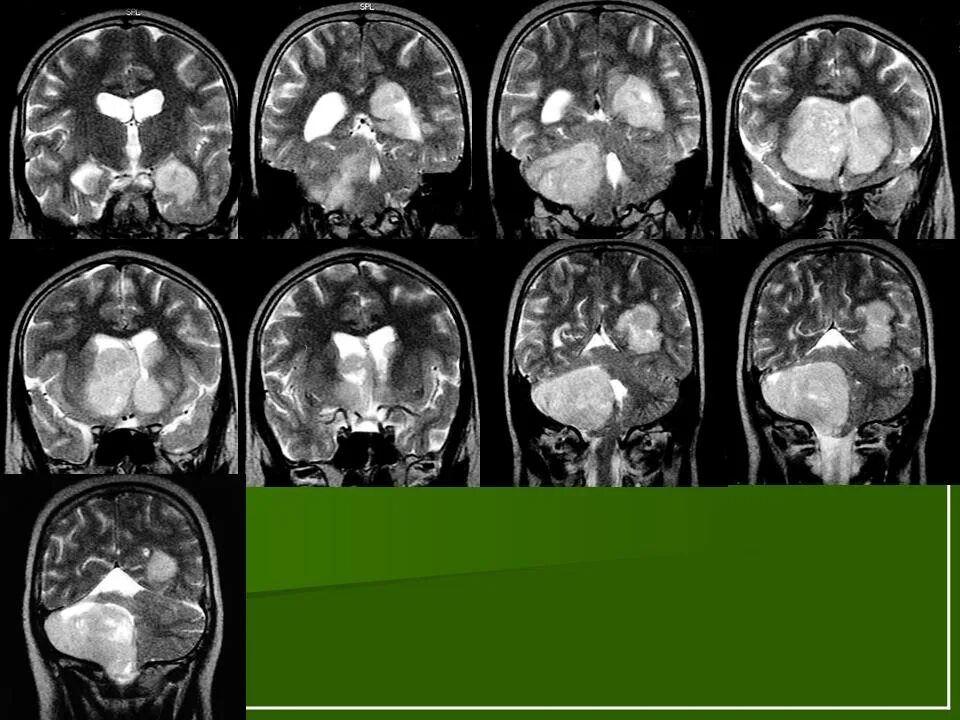

Медуллобластома это